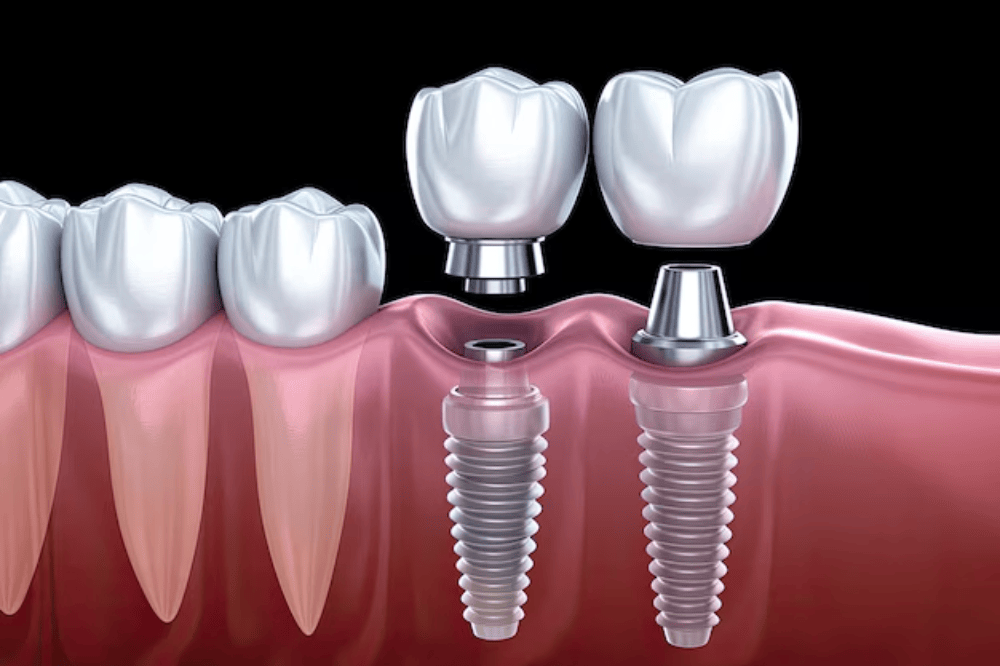

Dental Implant in College Road Nashik | Care32 Dental Clinic

Dental implants have revolutionized modern dentistry, offering a permanent and effective solution for missing teeth. If ...

Dental Implant in Canada Corner Nashik | Care32 Dental Clinic

A confident smile plays a crucial role in our self-esteem and overall well-being. However, missing teeth can lead to ora...